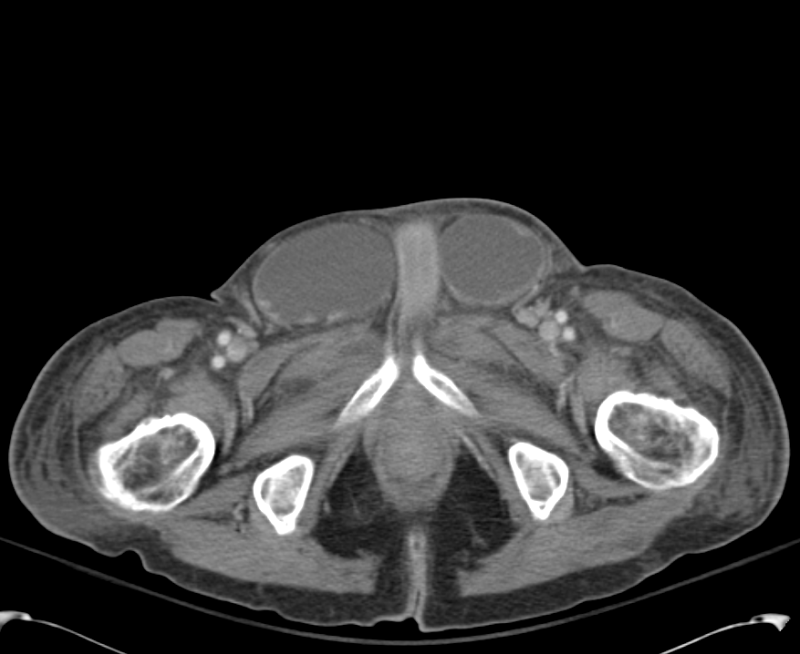

Diagnosis of Inguinal Region Hernias with Axial CT The Lateral Differential Diagnosis Inguinal Hernia Collectively, inguinal and femoral hernias are known as groin hernias. An inguinal hernia occurs when abdominal or pelvic contents protrude through a dilated internal ring or attenuated inguinal floor. If the mass extends into the scrotum, consider a hydrocoele, varicocoele, or a testicular malignancy. Involvement of the bladder with an inguinal hernia is estimated to occur in 1% to 4%. Differential Diagnosis Inguinal Hernia.

Diagnosis of Inguinal Region Hernias with Axial CT The Lateral Differential Diagnosis Inguinal Hernia These include femoral hernia, saphena varix, inguinal lymphadenopathy, lipoma, or groin abscess. Involvement of the bladder with an inguinal hernia is estimated to occur in 1% to 4% of all inguinal hernias and is more. A direct inguinal hernia is a protrusion of tissue through the posterior wall of the inguinal canal, medial to the inferior epigastric vessels (figure 2. Differential Diagnosis Inguinal Hernia.

ctap_0002_BLInguinalHernias Differential Diagnosis of Differential Diagnosis Inguinal Hernia There are several differential diagnoses for a lump in the groin. A direct inguinal hernia is a protrusion of tissue through the posterior wall of the inguinal canal, medial to the inferior epigastric vessels (figure 2 1), whereas an indirect inguinal. If the mass extends into the scrotum, consider a hydrocoele, varicocoele, or a testicular malignancy. An inguinal hernia occurs. Differential Diagnosis Inguinal Hernia.

ctap_0003_LargeRInguinalHernia Differential Diagnosis of Differential Diagnosis Inguinal Hernia Inguinal hernias may cause a burning, gurgling, or aching sensation in the groin, and a heavy or dragging sensation may worsen toward the end. A direct inguinal hernia is a protrusion of tissue through the posterior wall of the inguinal canal, medial to the inferior epigastric vessels (figure 2 1), whereas an indirect inguinal. An inguinal hernia occurs when abdominal. Differential Diagnosis Inguinal Hernia.